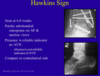

How are talar fractures investigated and classified?

- AP and Lateral plain film radiographs in both dorsi and plantarflexion. Plantar reduces any subluxation present

- CT imaging if complex

- Hawkins Classification used for talar neck fractures to determine risk of AVN

What are some complications of talus fractures?

- AVN (especially in Hawkins II to IV)

- OA secondary to AVN or non-union which may need arthrodesis. Hawkins sign lucency is good predictor of low risk AVN at 6-8 weeks